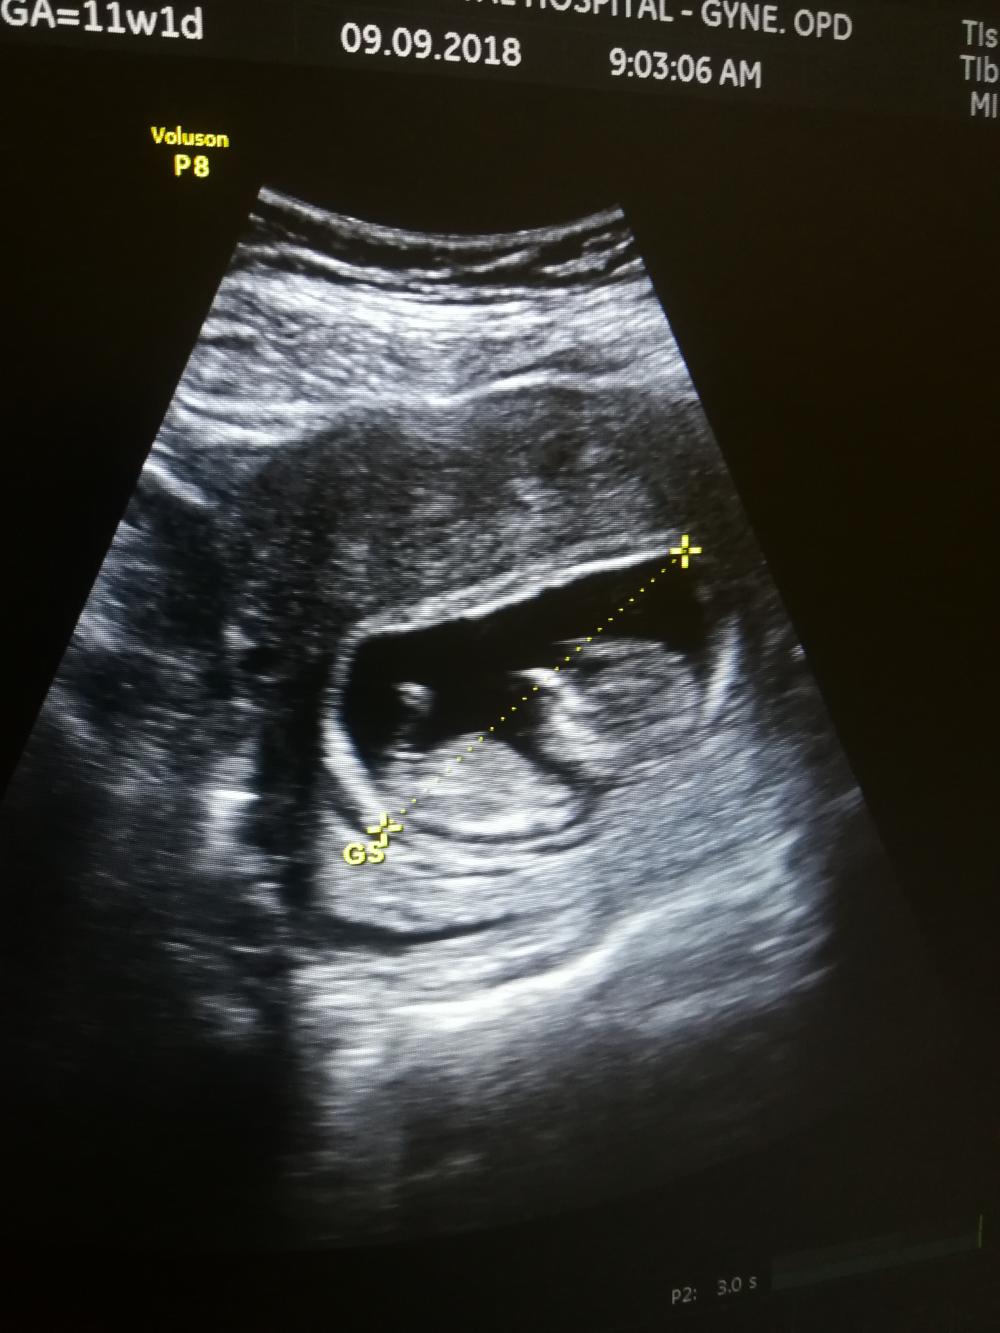

انا سوناري بسبع اسابيع وخمس ايام

واضح شكل جنين راس وكان فيه اطراف خفيفه

يعني ولد؟!؟!